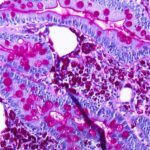

Las infecciones intraperitoneales suelen deberse a la rotura de una barrera anatómica normal que puede producirse por diversas causas por ejemplo cuando el apéndice, un divertículo o una úlcera se…